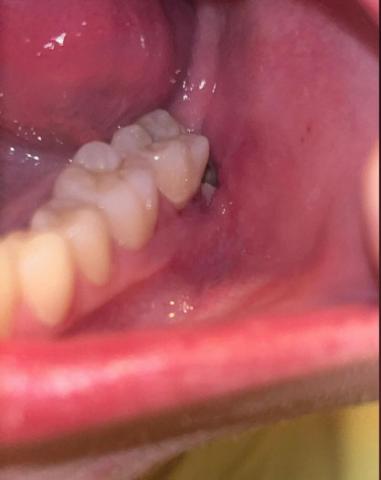

The image shows a posterior lower molar area with an open extraction socket behind the last visible tooth. Surrounding gum tissue appears reddish and inflamed, with possible food debris or clot disruption. This presentation is commonly associated with delayed healing or early dry socket risk.

Tooth & Socket Area

-

Missing posterior molar (recent extraction site)

Socket appears partially open

Possible loss or thinning of blood clot

Mild grayish area inside socket (possible debris or exposed bone)

Gum & Soft Tissue

Redness around socket margins

Mild swelling of surrounding gingiva

No visible pus, but inflammation is present

Adjacent Teeth

Neighboring molar appears intact

No obvious caries on adjacent tooth

Gingival margin near adjacent tooth slightly irritated

Primary Diagnosis

Delayed post-extraction healing with risk of dry socket (alveolar osteitis)